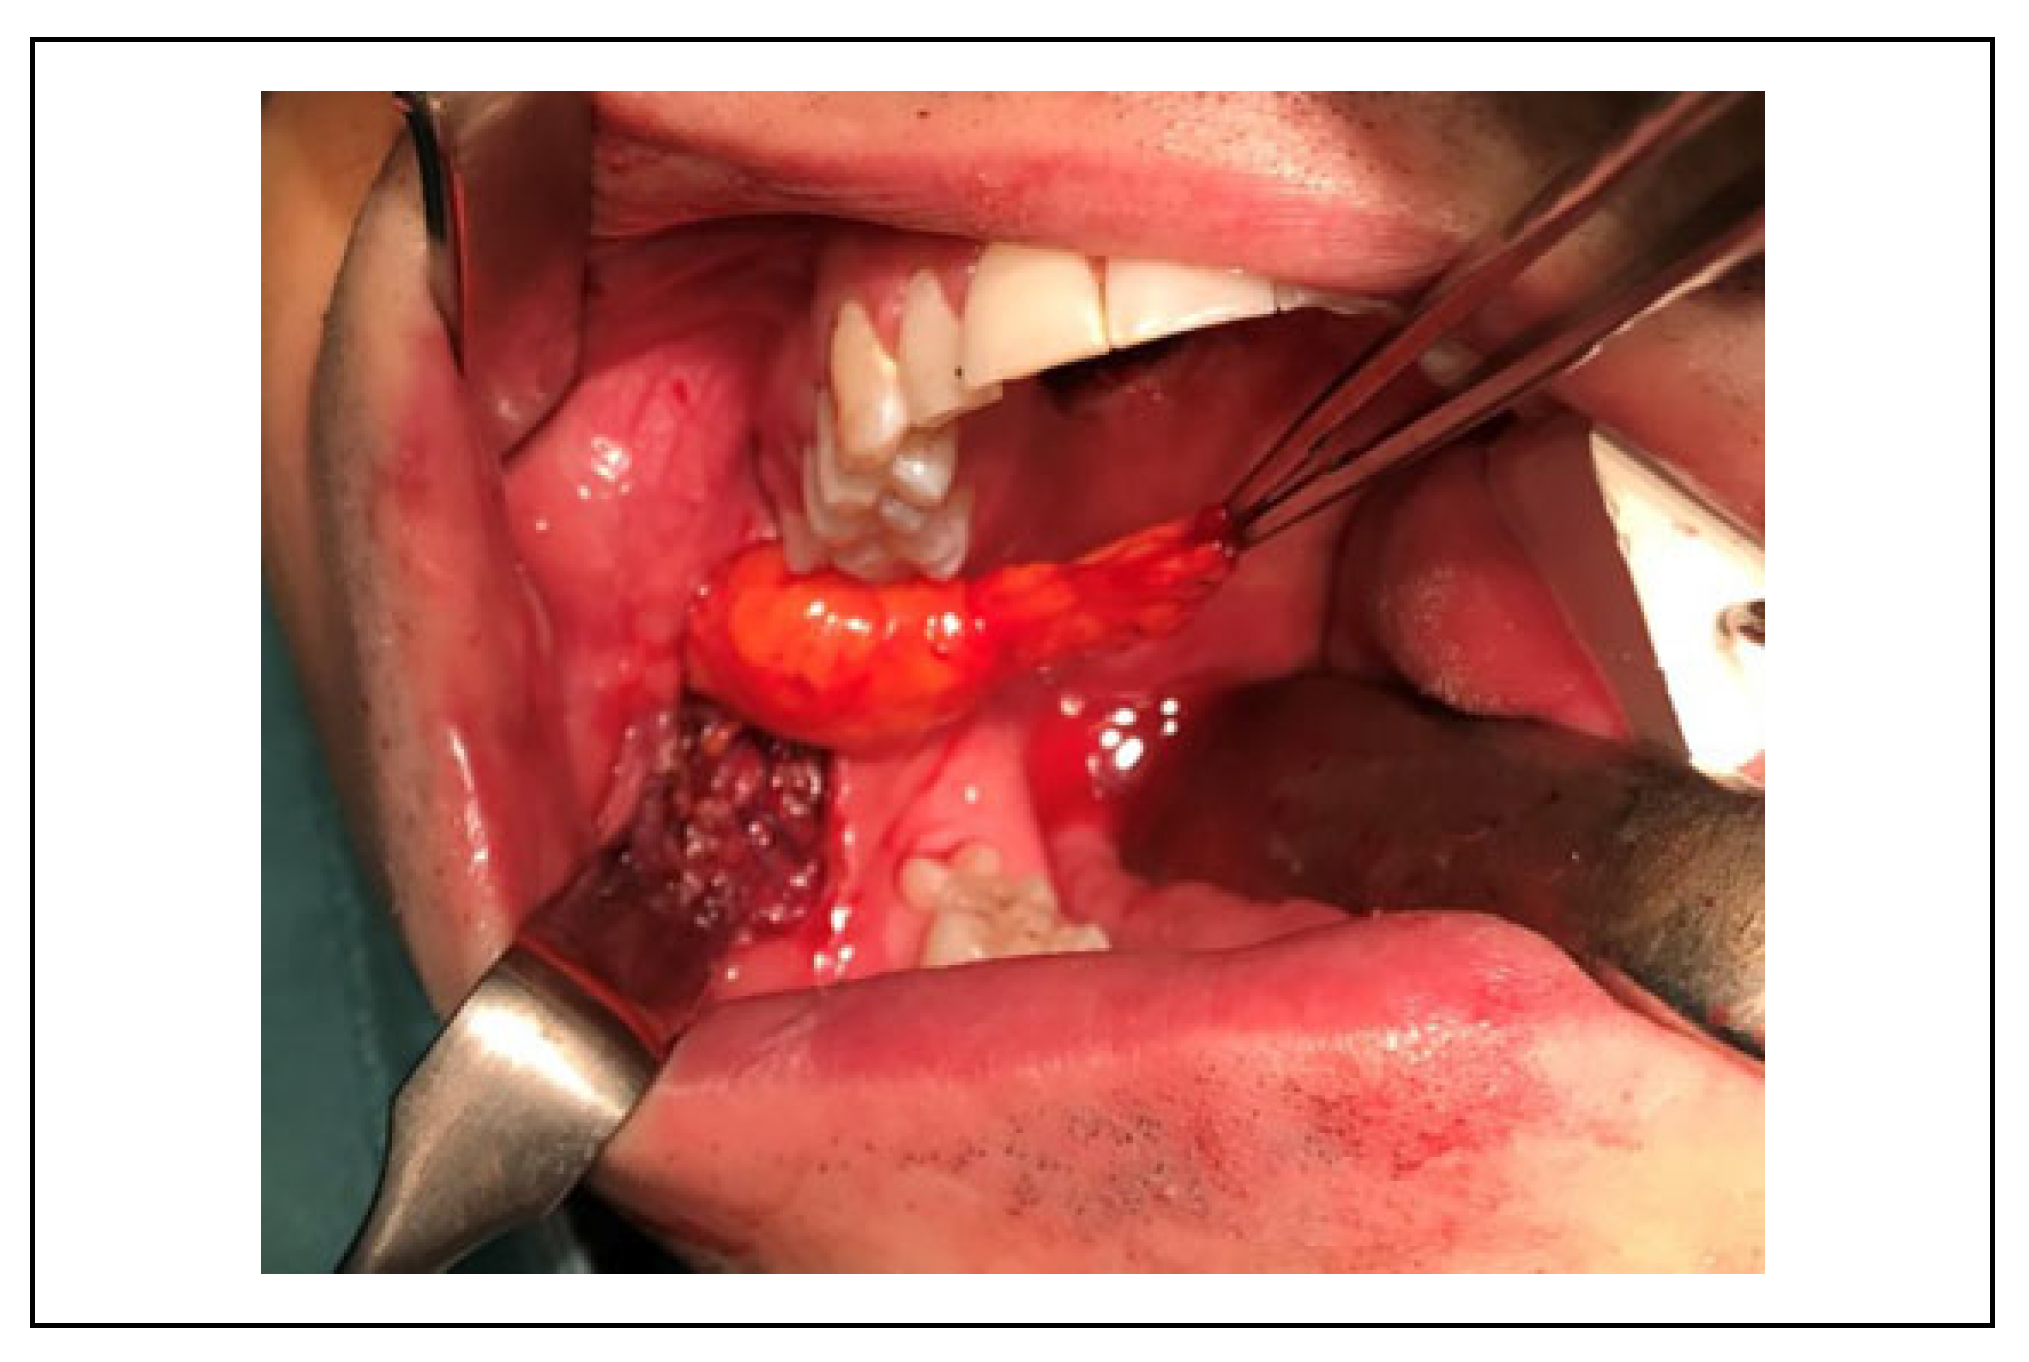

Surgical Technique